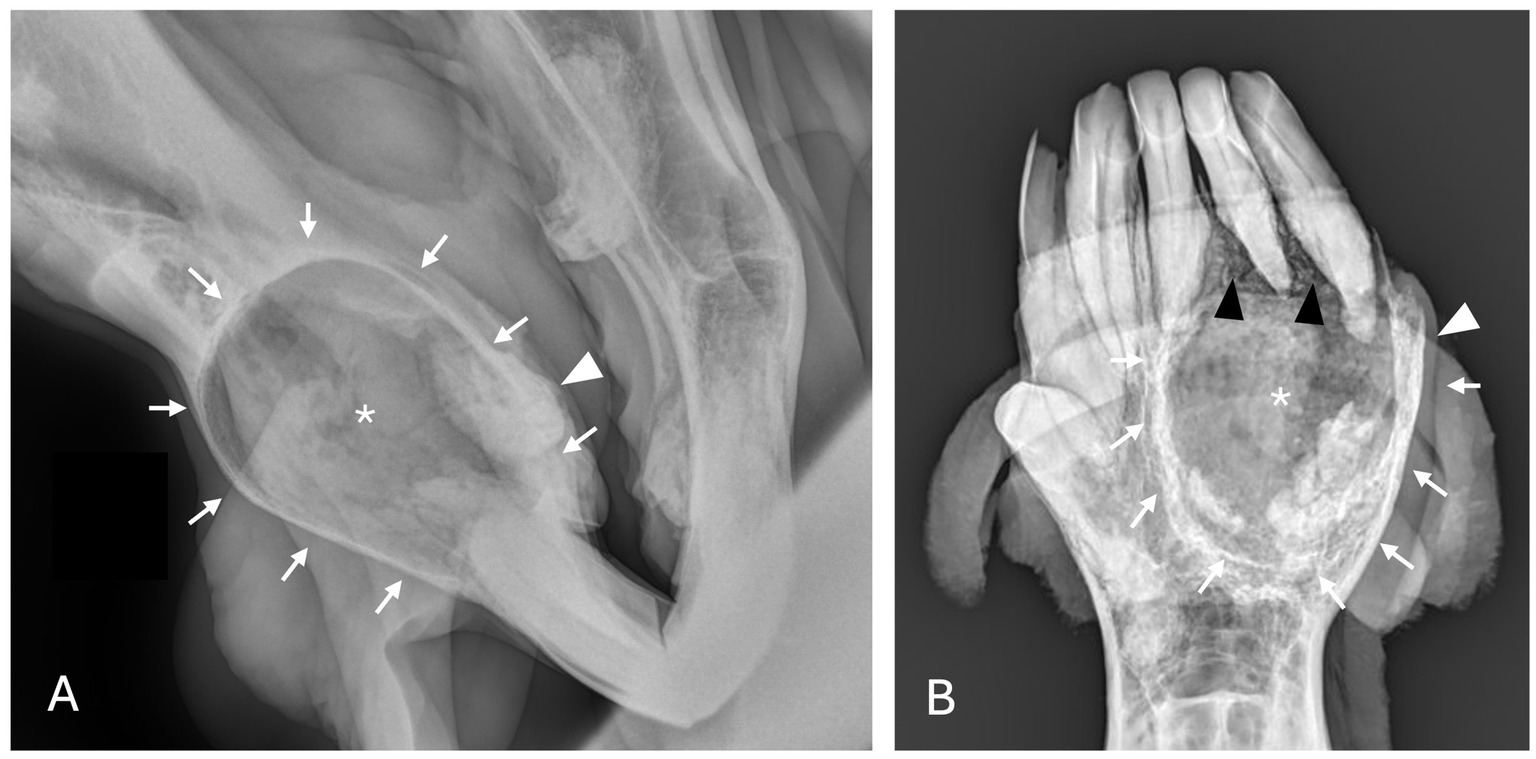

Radiographic findings are reported based on lesion type (Table 4) and location (Table 5). The most prevalent radiographic finding was tooth involvement in 16/17 (94.1%) cases followed by multiloculated lesions and increased soft tissue opacity in 14/17 (82.4%) cases, respectively (Figures 2–4). Rarefication of the surrounding bone (cortical thinning) was the third most common imaging finding identified in 13/17 (76.5%) of cases. All lesions had tooth involvement except for 1 bone cyst lesion. Radiographically unerupted teeth were 100% associated with dentigerous cysts (6/6) of which 83% (5/6) of the unerupted teeth were dysplastic (Figure 2). Thirty-three percent (2/6) of dentigerous cysts were associated with additional irregular dental material, and both of these lesions were located within the rostral maxilla (Figure 2). Dysplastic teeth also occurred in 2/6 (33%) of bone cysts (Figure 3). Abnormal dental findings were more closely linked to lesion type than location in the mouth.

Figure 2. Dentigerous cyst radiographic findings. (A,B) Case 2 multiloculated, well circumscribed dentigerous cyst containing irregular dental material (black arrows) associated with unerupted and dysplastic 104 (white asterisk), with rarefication of surrounding bone (white star) Images courtesy of Dr. Robert Baratt. (C) Case 9 multiloculated, well circumscribed dentigerous cyst containing irregular dental material (black arrows) associated with unerupted and dysplastic 306 (white asterisk) with osteosclerosis of adjacent bone (white arrowheads) Image courtesy of Easley equine dentistry. (D) Case 16 unilocular, well circumscribed dentigerous cyst associated with unerupted and dysplastic 307 (white asterisk), with osteosclerosis of adjacent bone (white arrowheads), and sunburst reaction (white arrows).

Rarefication of the surrounding bone was the most common radiographic bony change identified in 13/17 (76.5%) of cases (Figure 2). Osteosclerosis of adjacent bone occurred in 7/17 (41.2%) of cases while osteolysis of adjacent bone occurred in 6/17 (35.3%) of cases (Figure 5). Rarefication of the surrounding bone was most commonly associated with dentigerous cysts (5/6; 83.3%) and bone cysts (5/6; 83.3%). Osteosclerosis of adjacent bone was observed most frequently in the body of the mandible with 5/7 (71.4%) of cases affected. Osteolysis of adjacent bone was most frequently observed in the caudal maxilla/paranasal sinuses (3/5; 60%) and in bone cysts (4/6; 66.6%). Dentigerous cysts were the only type of lesion in this study to have an osteoproductive appearance with 4/6 (66.6%) cases of dentigerous cysts affected. Sunburst reaction was observed in a single case of a mandibular body dentigerous cyst (Figure 2).

On diagnostic imaging, lesions were identified as predominately multiloculated with increased soft tissue opacity (both 82.4%). On radiographs and CT, this change in radiopacity/attenuation indicated the presence of either soft tissue or a uniform fluid. Aspiration or surgical penetration into the site was the main way to determine which was present. Tooth involvement was identified in 94.1% of cases. The only case that did not have dental involvement was a bone cyst of the mandibular body that did not contact the apices of the mandibular premolar and molar teeth. Rarefication of the surrounding bone was the most common bony change, and it occurred in 76.5% of cases. This was expected due to the expansile and benign behavior of cystic masses. CT findings associated with equine paranasal sinus cysts reported 100% cancellous and 50% cortical bone loss adjacent to sinus cysts in 8 horses (24). A retrospective study assessing the clinical presentation, CT findings and outcome of equine odontogenic tumors in 11 horses found that all tumors were associated with maxillary/mandibular bone expansion, alveolar and cortical bone lysis, and cortical bone thinning (25). Cortical bone thickening was observed in 8/11 horses (72.7%) with odontogenic tumors compared to osteosclerosis of adjacent bone in 7/17 (41.2%) cases with non-neoplastic masses in the present study (25). Periosteal proliferation also occurred commonly in 7/11 horses (63.6%) with odontogenic tumors. Periosteal proliferation (documented as sunburst reaction in this study) was observed in a single case of a mandibular body dentigerous cyst associated with an unerupted left mandibular fourth premolar tooth diagnosed in an 18-year-old Warmblood gelding. Further studies with larger case numbers will be needed to determine the association of periosteal reaction with cystic masses.